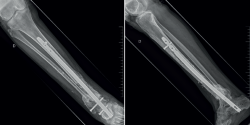

Durante las semanas siguientes comienza una evolución tórpida, con supuración a través de la herida quirúrgica, aumento de la temperatura local, fiebre y dolor. Se envían a cultivar muestras de exudado que se positivizan para Staphylococcus aureus sensible a la meticilina (SAMS), por lo que se comienza una pauta con vancomicina 1 g cada 12 horas y ceftazidima 2 g cada 8 horas. Se empiezan a realizar curas seriadas en quirófano combinándolas con terapia de presión negativa con sistema VAC (vacuum assisted closure). Termina por exponerse el material de osteosíntesis. Un mes tras la primera intervención se decide realizar la retirada del material y la fijación con un fijador externo monolateral articulado XCaliber (Figura 3); se necesita también la intervención por parte de cirugía plástica para la cobertura de los tejidos expuestos. Se toman muestras intraoperatorias, cuyos cultivos son negativos. Comienza una pauta de antibioterapia de amplio espectro con cloxacilina + rifampicina intravenosa (i.v.) durante su ingreso. Al alta continúa con una pauta de rifampicina 600 mg y levofloxacino 500 mg cada 24 horas durante las siguientes 2 semanas. Antes del alta se objetiva la normalización del estado clínico y analítico.

El fijador se mantiene durante 5 meses y es retirado tras observarse consolidación parcial con puentes óseos en la TAC. Durante los meses siguientes se observa una deformidad progresiva en varo del miembro y una no consolidación de la fractura (Figura 4). Se realiza una gammagrafía que es compatible con pseudoartrosis. Finalmente, 1 año tras la fractura ingresa en el hospital por pseudoartrosis con sospecha de osteomielitis crónica.

Figura 4. Radiografías A y B: deformidad del tobillo un mes tras la retirada del fijador externo; C y D: 5 meses tras la retirada.